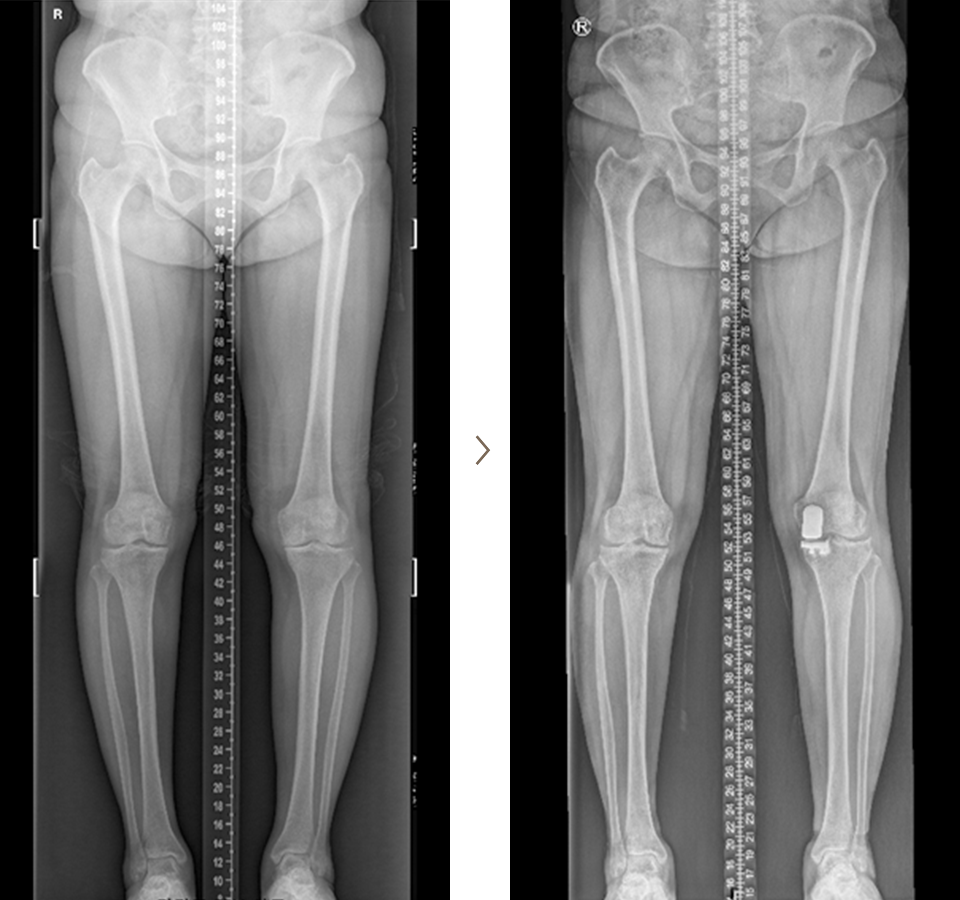

휜다리 교정술 치료 사례

- 환자 동의하에 게시된 이미지입니다.

<수술전 엑스레이 사진>

<수술후 엑스레이 사진>